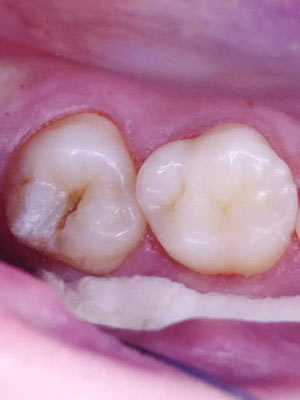

窩溝封閉前后

窩溝封閉前

窩溝封閉后

易患齲的深窩溝和早起齲損

高質(zhì)量的封閉,對于任何年齡的都有益